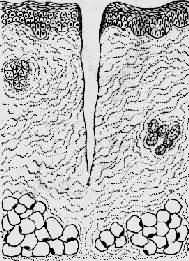

1.一般愈合(healing by first intention)见于组织缺损少、创缘整齐、无感染、经粘合或缝合后创面对合严密的伤口,例如手术切口。这种伤口中只有少量血凝块,炎症反应轻微,表皮再生在24~48小时内便可将伤口覆盖。肉芽组织在第三天就可从伤口边缘长出并很快将伤口填满,5~6天胶原纤维形成(此时可以拆线),约2~3周完全愈合,留下一条线状瘢痕。一期愈合的时间短,形成瘢痕少(图2-5)。

1.创缘整齐,组织破坏少

2.经缝合,创缘对合,炎症反应轻

3.表皮再生,少量肉芽组织从伤口缘长入

4.愈合后少量疤痕形成

图2-5 创伤一期愈合模式图